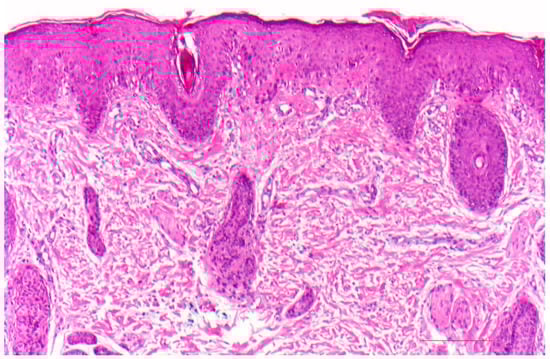

10. Peeling Skin Disease

10.1. Histology